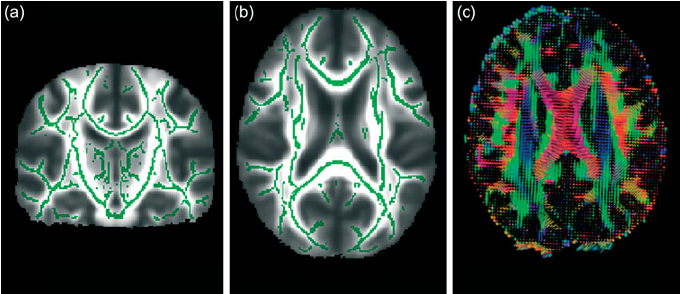

Now there are many ways to answer that. First, we need to go with conventions We start by answering at a more fundamental level, you have two types of physicists, fundamental physicists and applied physicists. What is the main difference between the two? Arguably the same as a theoretical mathematician and applied mathematician. Which means, that while both applied and theoretical physicists can work on the same subject, an applied physicist would work on a subject in order to find a pratical use out of it. Now while this seems similar to engineering, it is not exactly the same thing, since an applied physicist will most likely be doing research on the physics of some thing, and later may find some use for it. A good example would be physicists Lauterbur and Mansfield, which applied the physics of nuclear spin and magnetic resonance to medical imaging, completely revolutionizing the field. On the same note, a fundamental physicist would also be researching the physics behind some particular phenomena, while not being particularly interested in the use it may have, they would doing research just for the sake of knowledge and physics. Using spin again, a good example would be physicists Bloch and Purcell, which found a mathematical model that could describe the behavior of nuclei under magnetic fields, and the phenomena of magnetic resonance that would occur.

We also have Condensed Matter Physics, that studies condensed matter (like liquids and solids, and everything in between) and their physical properties. They study things like phase transitions and distributions of energy and states, something statistical physics, I guess. And they apply various fields of both classical and modern physics, like quantum mechanics. This field overlaps with others like Chemistry, and Biophysics (an applied physics) and has some cool things to be studied like superfluidity and superconductivity, and topological phase transitions. Usually the field is subdivided in Solid State Matter Physics and Soft Matter Physics. Now, while Physics doesn’t have a industry of its own (like the Chemical Industry) you can say that arguably, the most important field of Modern Physics to industry is CMPhysics, specially SSMatter Physics, because all of modern electronics is based on research in CMP. So, you can imagine that the applications usually involve nanotechnology, semiconductors, and oddly enough, or maybe not, even MRI (which kind of makes sense, thanks to superconductivity)